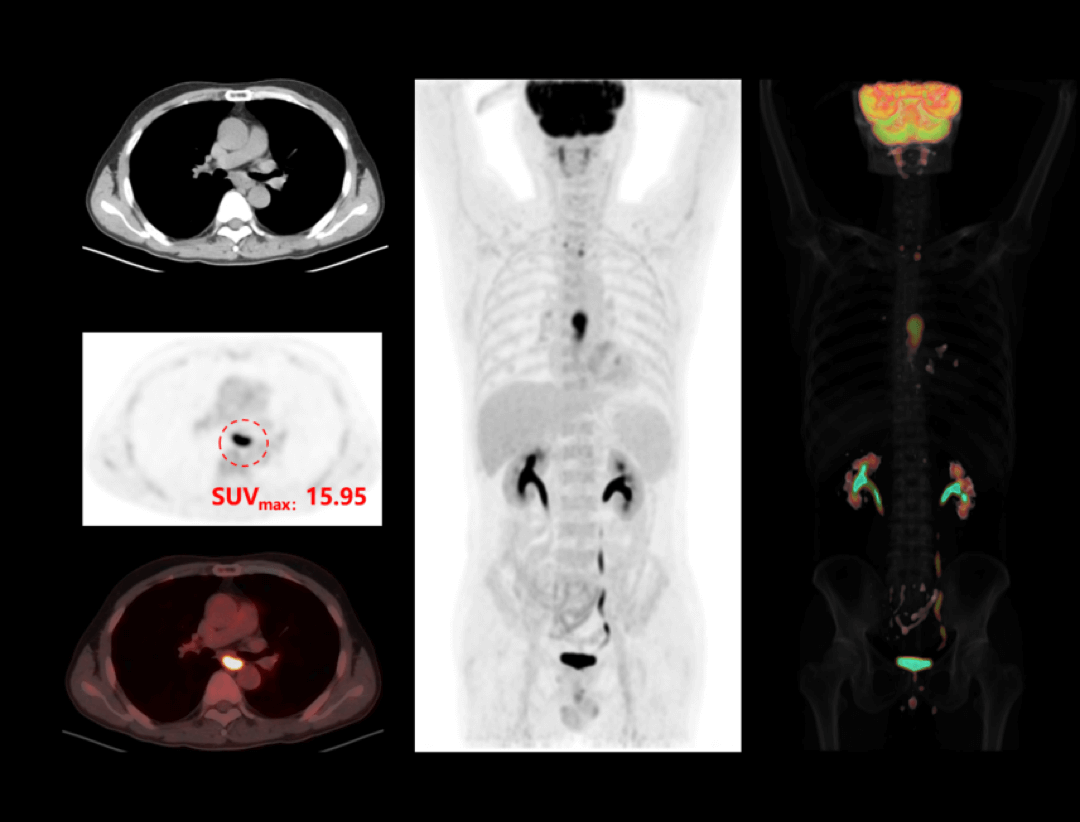

Cancer esofagian

Imagistica PET/CT oferă detalii esențiale pentru diagnosticarea și stadializarea cancerului esofagian, permițând evaluarea precisă a extensiei tumorale și monitorizarea răspunsului la tratament.

Cancer pulmonar

Investigațiile cu PET/CT digital oferă o evaluare precisă a cancerului pulmonar, sprijinind diagnosticarea timpurie, stadializarea corectă și monitorizarea răspunsului la tratament.